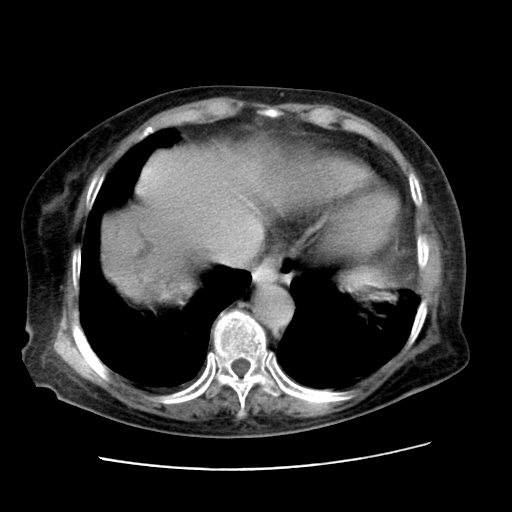

女,77.无不适

肝内胆管扩张,胆囊炎,胆囊窝积液。 右侧胸腔少量积液。

右侧胸腔少量积液(也可能是胸膜增厚不过是什么都一样)

胆囊未见明显显影

肝旁多发胆囊状液体影考虑肠腔积液基中部分囊状景不多外胆囊